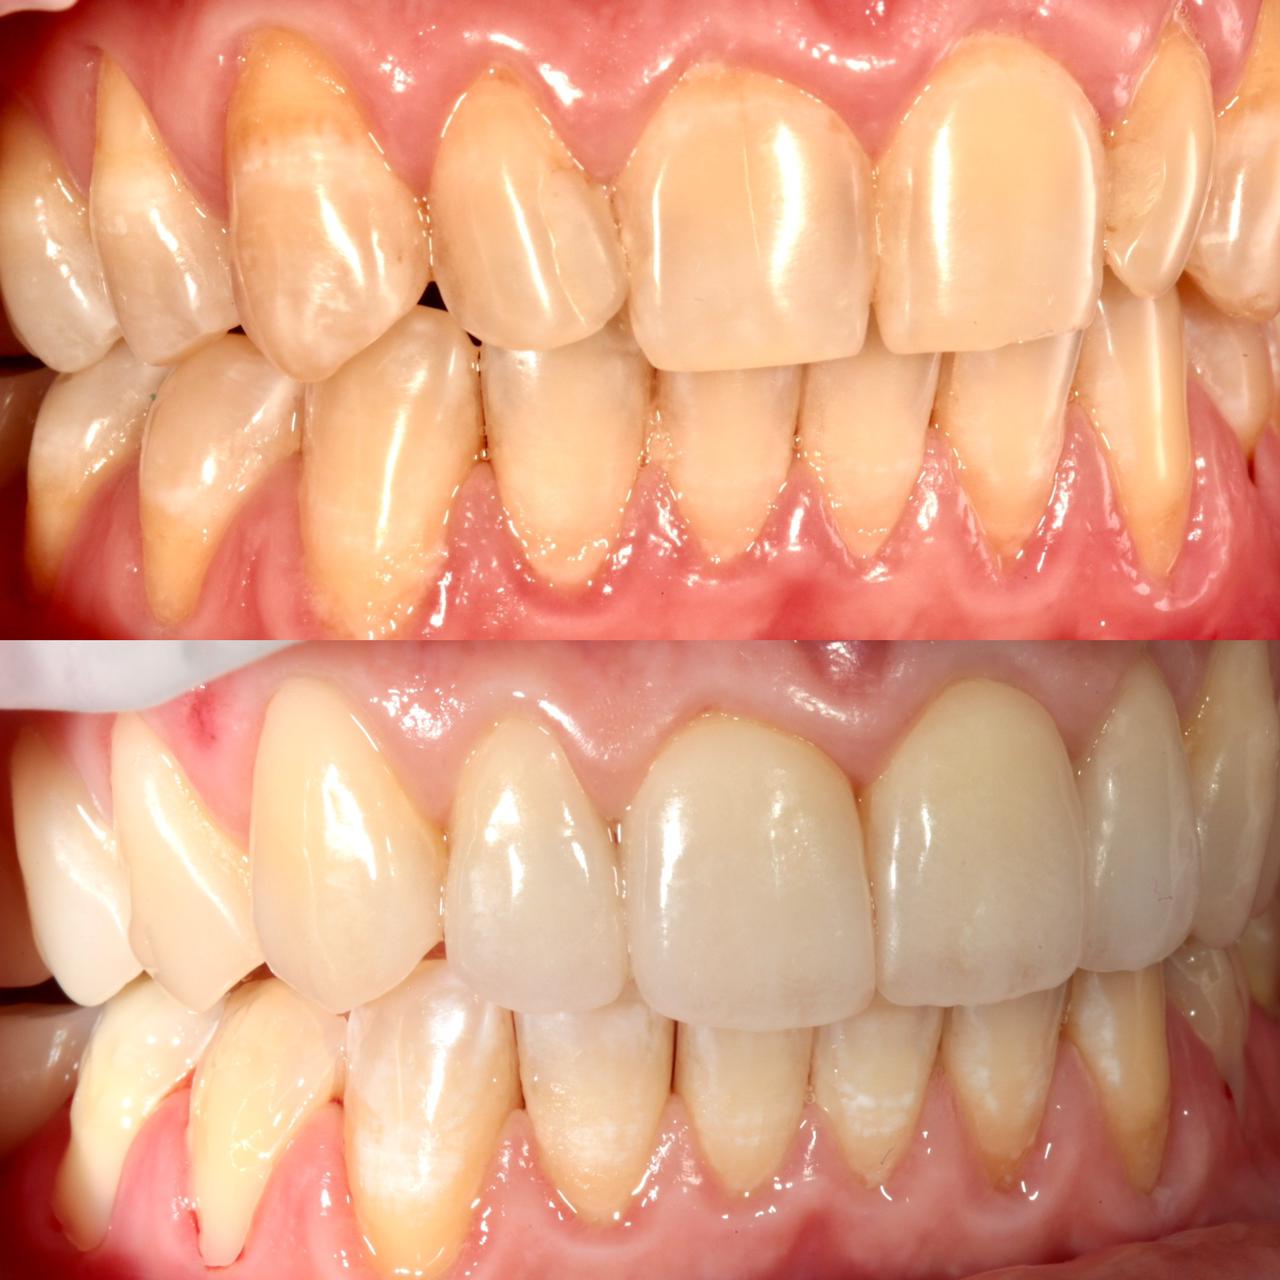

Примеры работ

Бережное и безболезненное лечение зубов

В работе используются современные технологии и премиальные светоотверждаемые материалы:

- Vitremer (Россия),

- Lumiglass.

- Filtek (США).